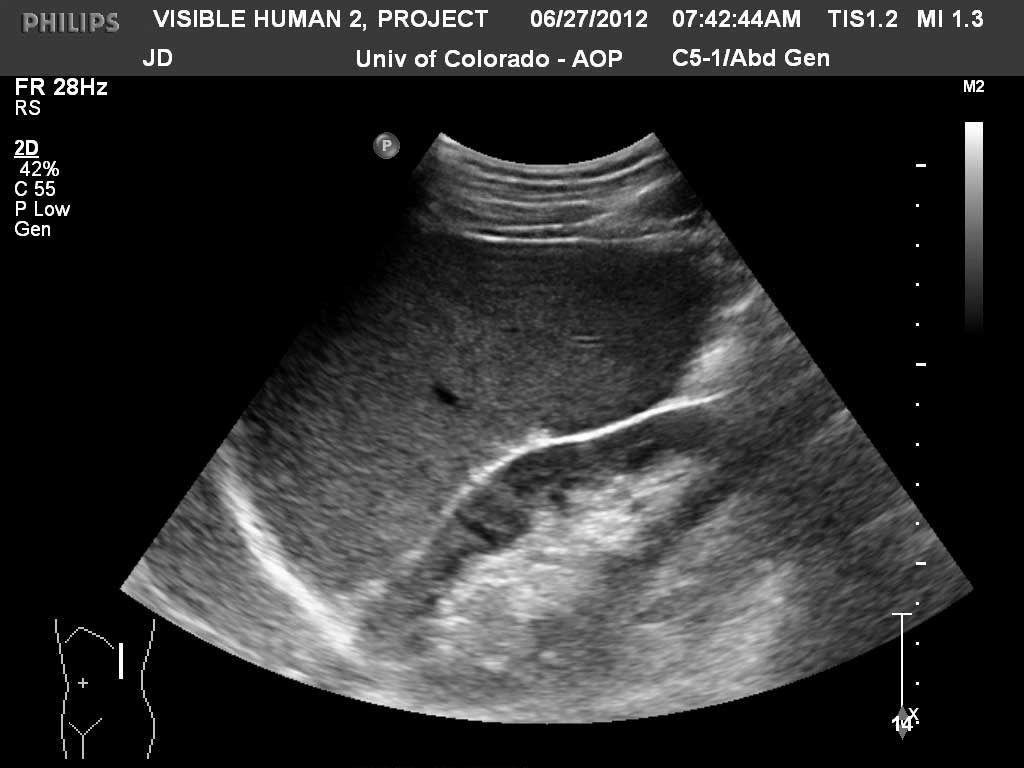

Long (Coronal) Spleen

Kidney

Renal Cortex

Renal Sinus Fat

Spleen